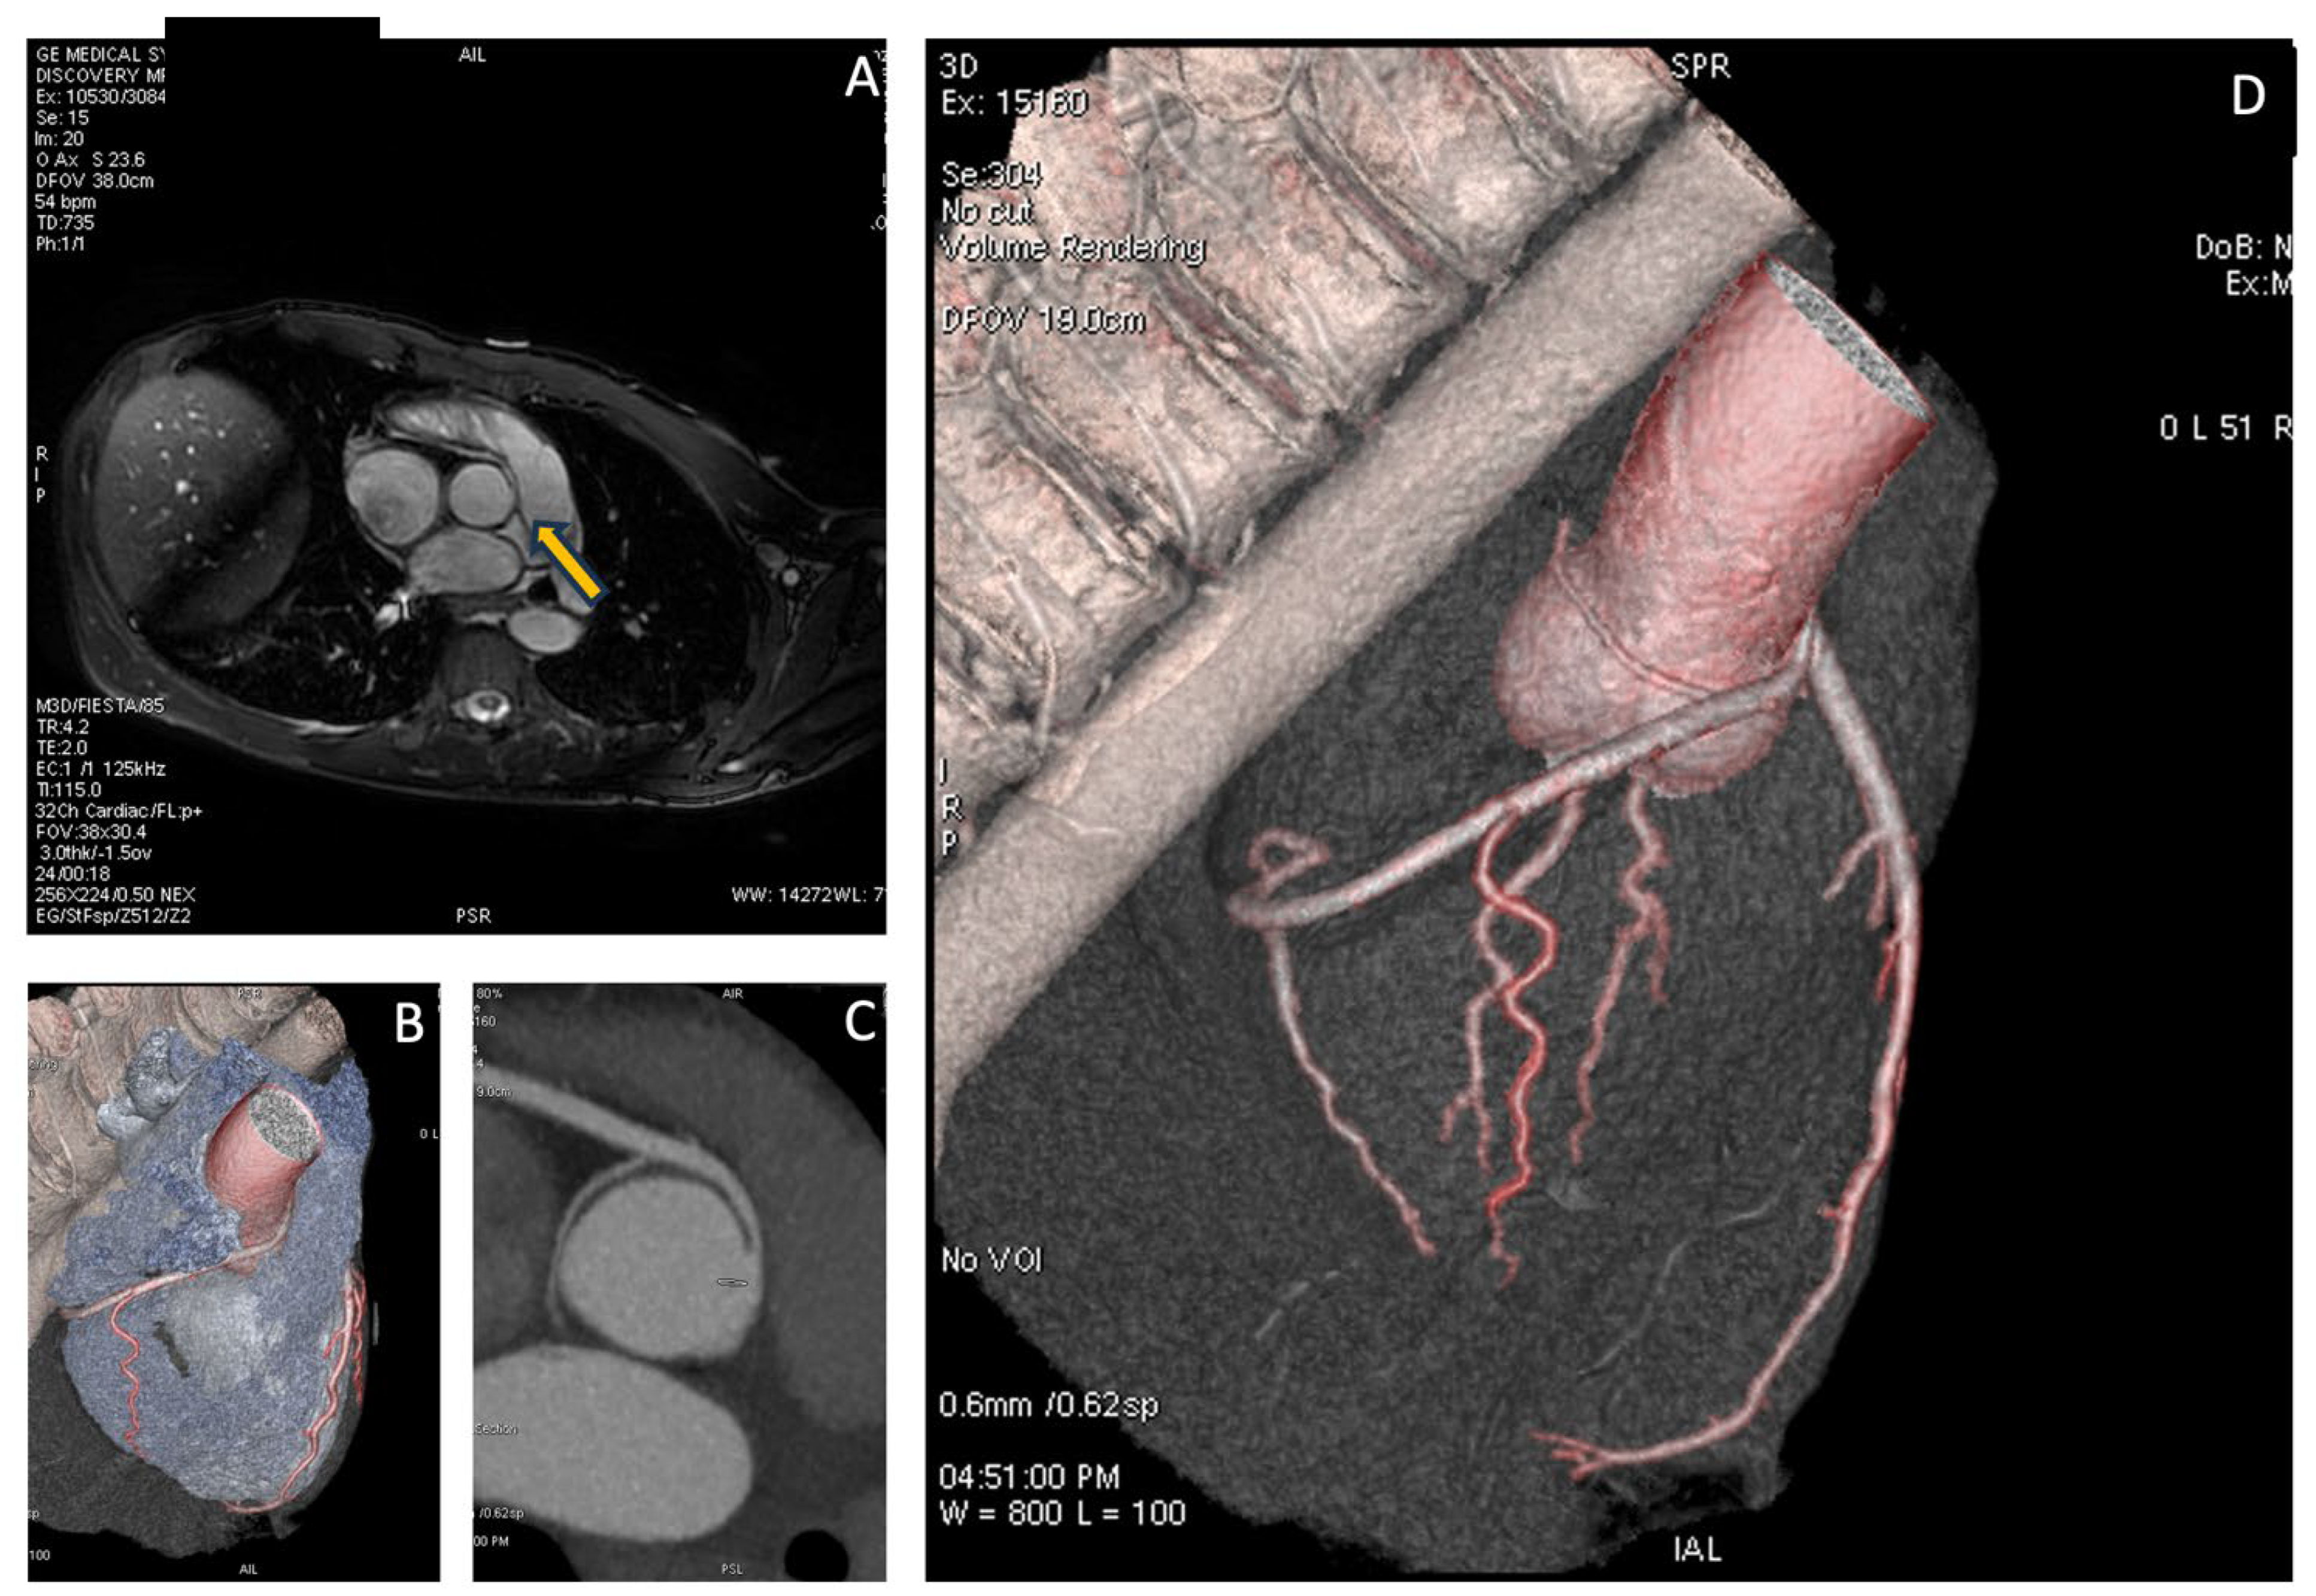

The patient subsequently underwent CMR, which showed normal biventricular volumes and function, with no evidence of myocardial fibrosis. However, specific sequences aimed at studying the origin of the coronary vessels identified the presence of a right coronary artery originating from the left Valsalva sinus. To complete the diagnostic assessment, the patient then underwent CCTA, which confirmed the diagnosis and revealed high-risk features, including the presence of a proximal intramural course and a “slit-like” ostial appearance, as illustrated in Figure 3.

Figure 3. In panel A, the cardiac MRI in the coronary study sequence shows the right coronary artery, indicated by the yellow arrow, originating from the left Valsalva sinus. In panels B, C and D similar images from the CCTA are shown, with the right coronary artery originating from the left sinus.